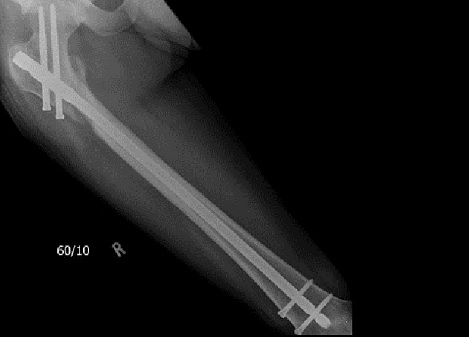

Fig8. - Open tibia fracture.

Fig8. - Treated with a monolateral external fixator.